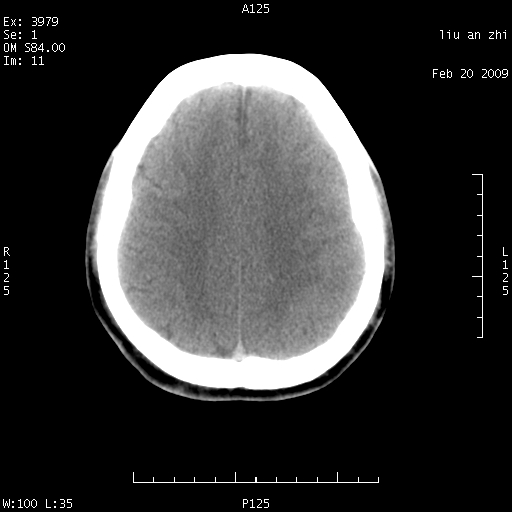

7天后复查头颅ct片:

小脑幕前后7天变化不明显,考虑正常,不考虑sah,7天应该基本吸收了。

ct18448的结果:mri检查左侧天幕下血肿

以下是引用深蓝一号在2009-3-9 16:22:00的发言:[br]ct18448的结果:mri检查左侧天幕下血肿。